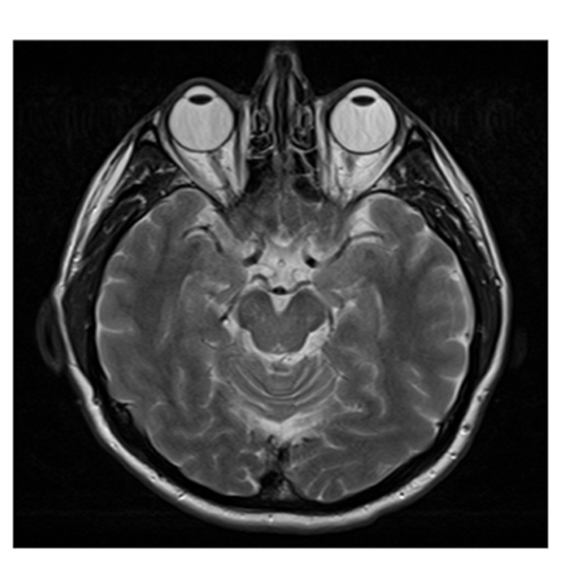

Horizontal (Axial): A plane that divides the brain into upper and lower sections.

Page 18: Techniques for Visualizing the Brain

Two primary categories of imaging techniques exist for examining the brain:

Structural Techniques:

CT Scan (Computed Tomography): Employs X-ray imaging to produce cross-sectional views of the brain, providing structural data.

MRI (Magnetic Resonance Imaging): Employs magnetic fields and radio waves to create detailed images of brain anatomy.

MRI Details:

Provides high-resolution images of the brain structures; aids in diagnosing various neurological diseases and conditions affecting brain integrity.